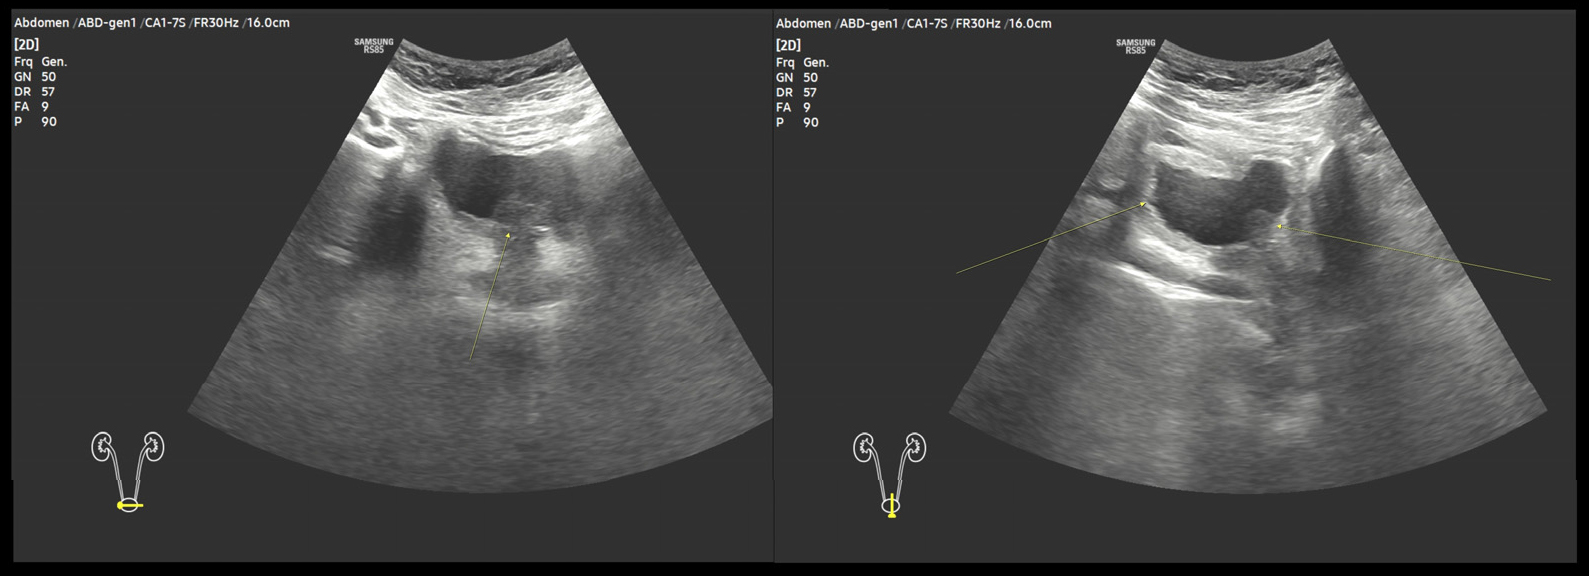

2.1. 신장 및 부신 방광 초음파

양측 신장의 장축의 길이는 10 cm으로 정상 신장이었으며 방광은 방광목 및 삼각대, 양 측벽, 전벽 등에 다발성 결절(multiple solid mass lesions)이 확인되었다. 결절은 주변과 경계가 분명하지 않았으며 내부에 석회화된 병변은 동반되지 않았다. 색도플러 초음파에서 병변내 혈류는 확인되지 않았다.